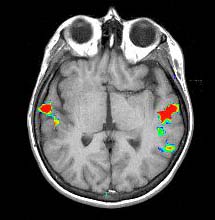

Activación auditiva verbal

Escuchar una historia de forma pasiva

Activación

Circunvolución supramarginal izquierda

Izquierda > Derecha Circunvoluciones de Heschl